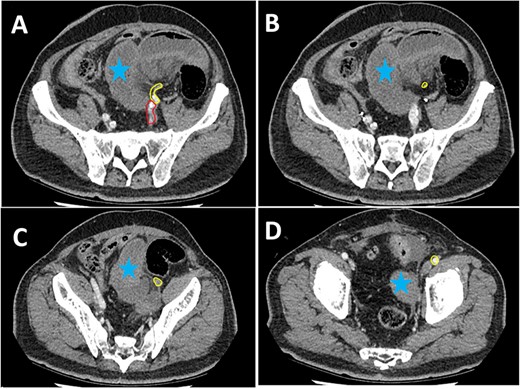

A 75-year-old male presented to our institution 4 months after RC for bladder cancer with acute abdominal pain and vomiting. Vital signs were within normal limits, the abdomen was distended and tender in the left lower quadrant. Significant biochemical derangements with metabolic acidosis and elevated lactate were demonstrated. A computed tomography (CT) scan of the abdomen and pelvis demonstrated a closed-loop SBO in the left lower quadrant with intrabdominal free fluid (Fig. 1). The right-sided ileal conduit appeared healthy.

CT scan axial slices demonstrating perihepatic free fluid (red arrow) and dilated loops of small bowel in the left iliac fossa (blue arrow). The ileal conduit (yellow arrow) in the right iliac fossa appears healthy.